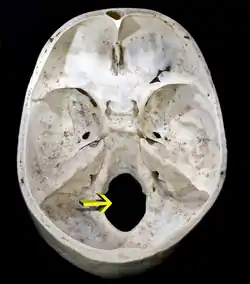

Foramen magnum

Upper surface of base of the skull. The hole indicated by an arrow is the foramen magnum

Occipital bone. Inner surface.